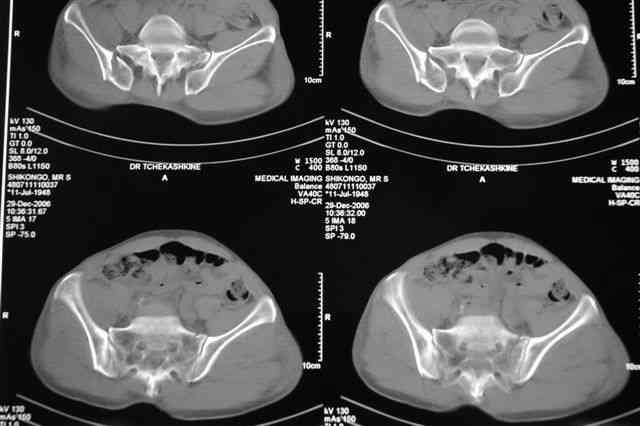

По-поводу фиксации таза спонгиозными винтами. Данный способ все-таки показан для фиксации повреждения крестцово-подвздошного сочленения или переломов крестца. Мне кажется, что в данной случае ситуация иная - имеется перелом "основания" крыла подвздошной кости (в который вовлечена и поверхность, составляющая крестцово-подвздошное сочленение). Не уверен, что фиксация данного повреждения (и заднего полукольца) винтами будет стабильной, так как именно на уровне 1-2 крестцовых позвонков (где обычно вводят винты) линия перелома уходит в латеральном направлении от крестцово-подвздошного сочленения.

PI>По-поводу фиксации таза спонгиозными винтами. Данный способ все-таки показан

для фиксации повреждения крестцово-подвздошного сочленения или переломов крестца. Мне кажется, что в данной случае ситуация иная - имеется перелом

"основания" крыла подвздошной кости (в который вовлечена и поверхность, составляющая крестцово-подвздошное сочленение). Не уверен, что фиксация данного повреждения (и заднего полукольца) винтами будет стабильной, так как

именно на уровне 1-2 крестцовых позвонков (где обычно вводят винты) линия перелома уходит в

латеральном направлении от крестцово-подвздошного сочленения.

Я просмотрел томограммы и у меня создалось впечатление, что винтам есть за что *зацепиться*. В сочетании с 5 мм Шанц винтами, проведенными через нижне-переднюю ость спереди назад через КП сочленения -стабильность тазового кольца должна восстановиться. - Это , конечно, при условии , что закрытая рнепозиция будет успешной.

PI>По-поводу репозиции костей таза. Производить репозицию костей все-таки необходимо. Пока я не встретил информации, сколько времени прошло с момента травмы, но одномоментно низвести правую половину таза может быть тяжело, учитывая и наличие перелома бедренной кости (что затруднит тракцию за нижние конечности).

Травма произошла 22 или 23 декабря, ко мне больной попал 26 декабря, 3 января -остеосинтез перелома бедра и внутр.лодыжки.

Да, я рассматривал и этот вариант контрлатеральной тяги в аппарате таз-бедро с целью устранения вертикального смещения правой половины таза, но

после КТ отказался от этой идеи - двусторонний перелом крестца в зоне 1 - алярная часть, при попытке низведения правого гемипелвиса теоретически есть вероятность смещения

фрагмента крестца слева.